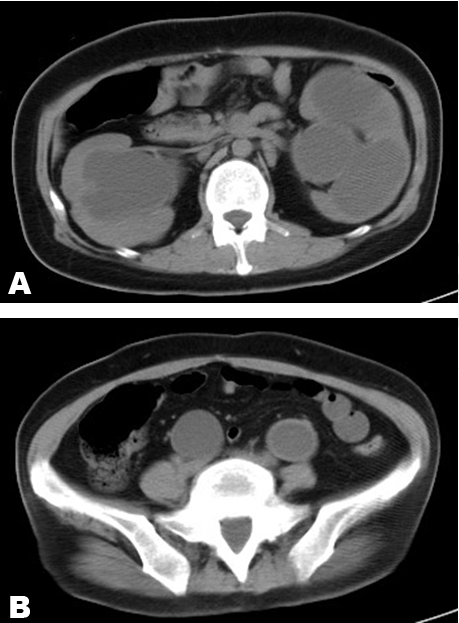

A 34-year-old female came to our hospital with complaints of anorexia and malaise that had persisted for approximately 10 days. She did not have abdominal or back tenderness, and her skin was dry. Her systolic blood pressure was 76 mmHg, and laboratory tests revealed an elevated creatinine level of 6.41 mg/dl, potassium level of 8.4 mEq/l, white blood cell count of 28,000/µl and C-reactive protein level of 17.98 mg/dl. She was admitted with diagnoses of urinary tract infection, acute kidney injury and hyperkalemia. At birth, she was diagnosed of schistorrhachis (Figure 1), and therefore, self-catheterization was performed. Abdominal computed tomography scan showed bilateral megaureters and hydronephrosis (Figure 2). Cystoscopy showed ends of both the ureters opening into the bladder. As her blood tests were abnormal (pH 7.360, serum HCO3 11.4 mmol/l), we performed hemodialysis once. Moreover, double J stents were placed in the ureters and antibiotic prophylaxis was administered. After treatment, her symptoms improved and blood tests became normal, and she was discharged. Based on this history, we diagnosed her as a case of neuropathic bladder secondary to schistorrhachis. | ||||||

A dilated ureter is considered as a megaureter, and any diameter of the ureter >8 mm is considered abnormal. Although the occurrence of megaureter is common in children, it is rare in adults. Megaureter can be classified as reflux, obstructed, and nonreflux-nonobstructed [1]. The causes of megaureter development are ureteropelvic junction obstruction, ureterovesical junction obstruction, neuropathic bladder, vesicoureterical reflux, high fetal urine output, and increased compliance of the fetal ureter. The presence of a megaureter could be considered when the patient has a urinary tract infection or hematuria. Moreover, ultrasonography scan, computed tomography, and magnetic resonance imaging scan can be used for its diagnosis. This was a case of reflux megaureter secondary to neuropathic bladder. Bilateral megaureters are rare in an adult. Medical treatment may include antibiotic prophylaxis for infection, anticholinergic medication, and clean intermittent catheterization for elevated detrusor leak point pressure. Surgical treatment may include ureteral plication or Infolding for moderately dilated ureters, and excisional tapering for massively dilated or thickened ureters. Treatment of secondary megaureter is conservative. However, treatment of primary megaureter may involve surgery or may be conservative [2]. | ||||||